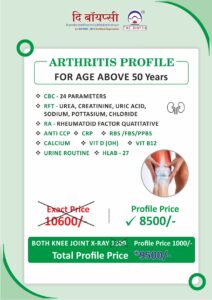

Our Health Packages

We Provide All Types of Diagnostics Services and its Health Pacakages also.